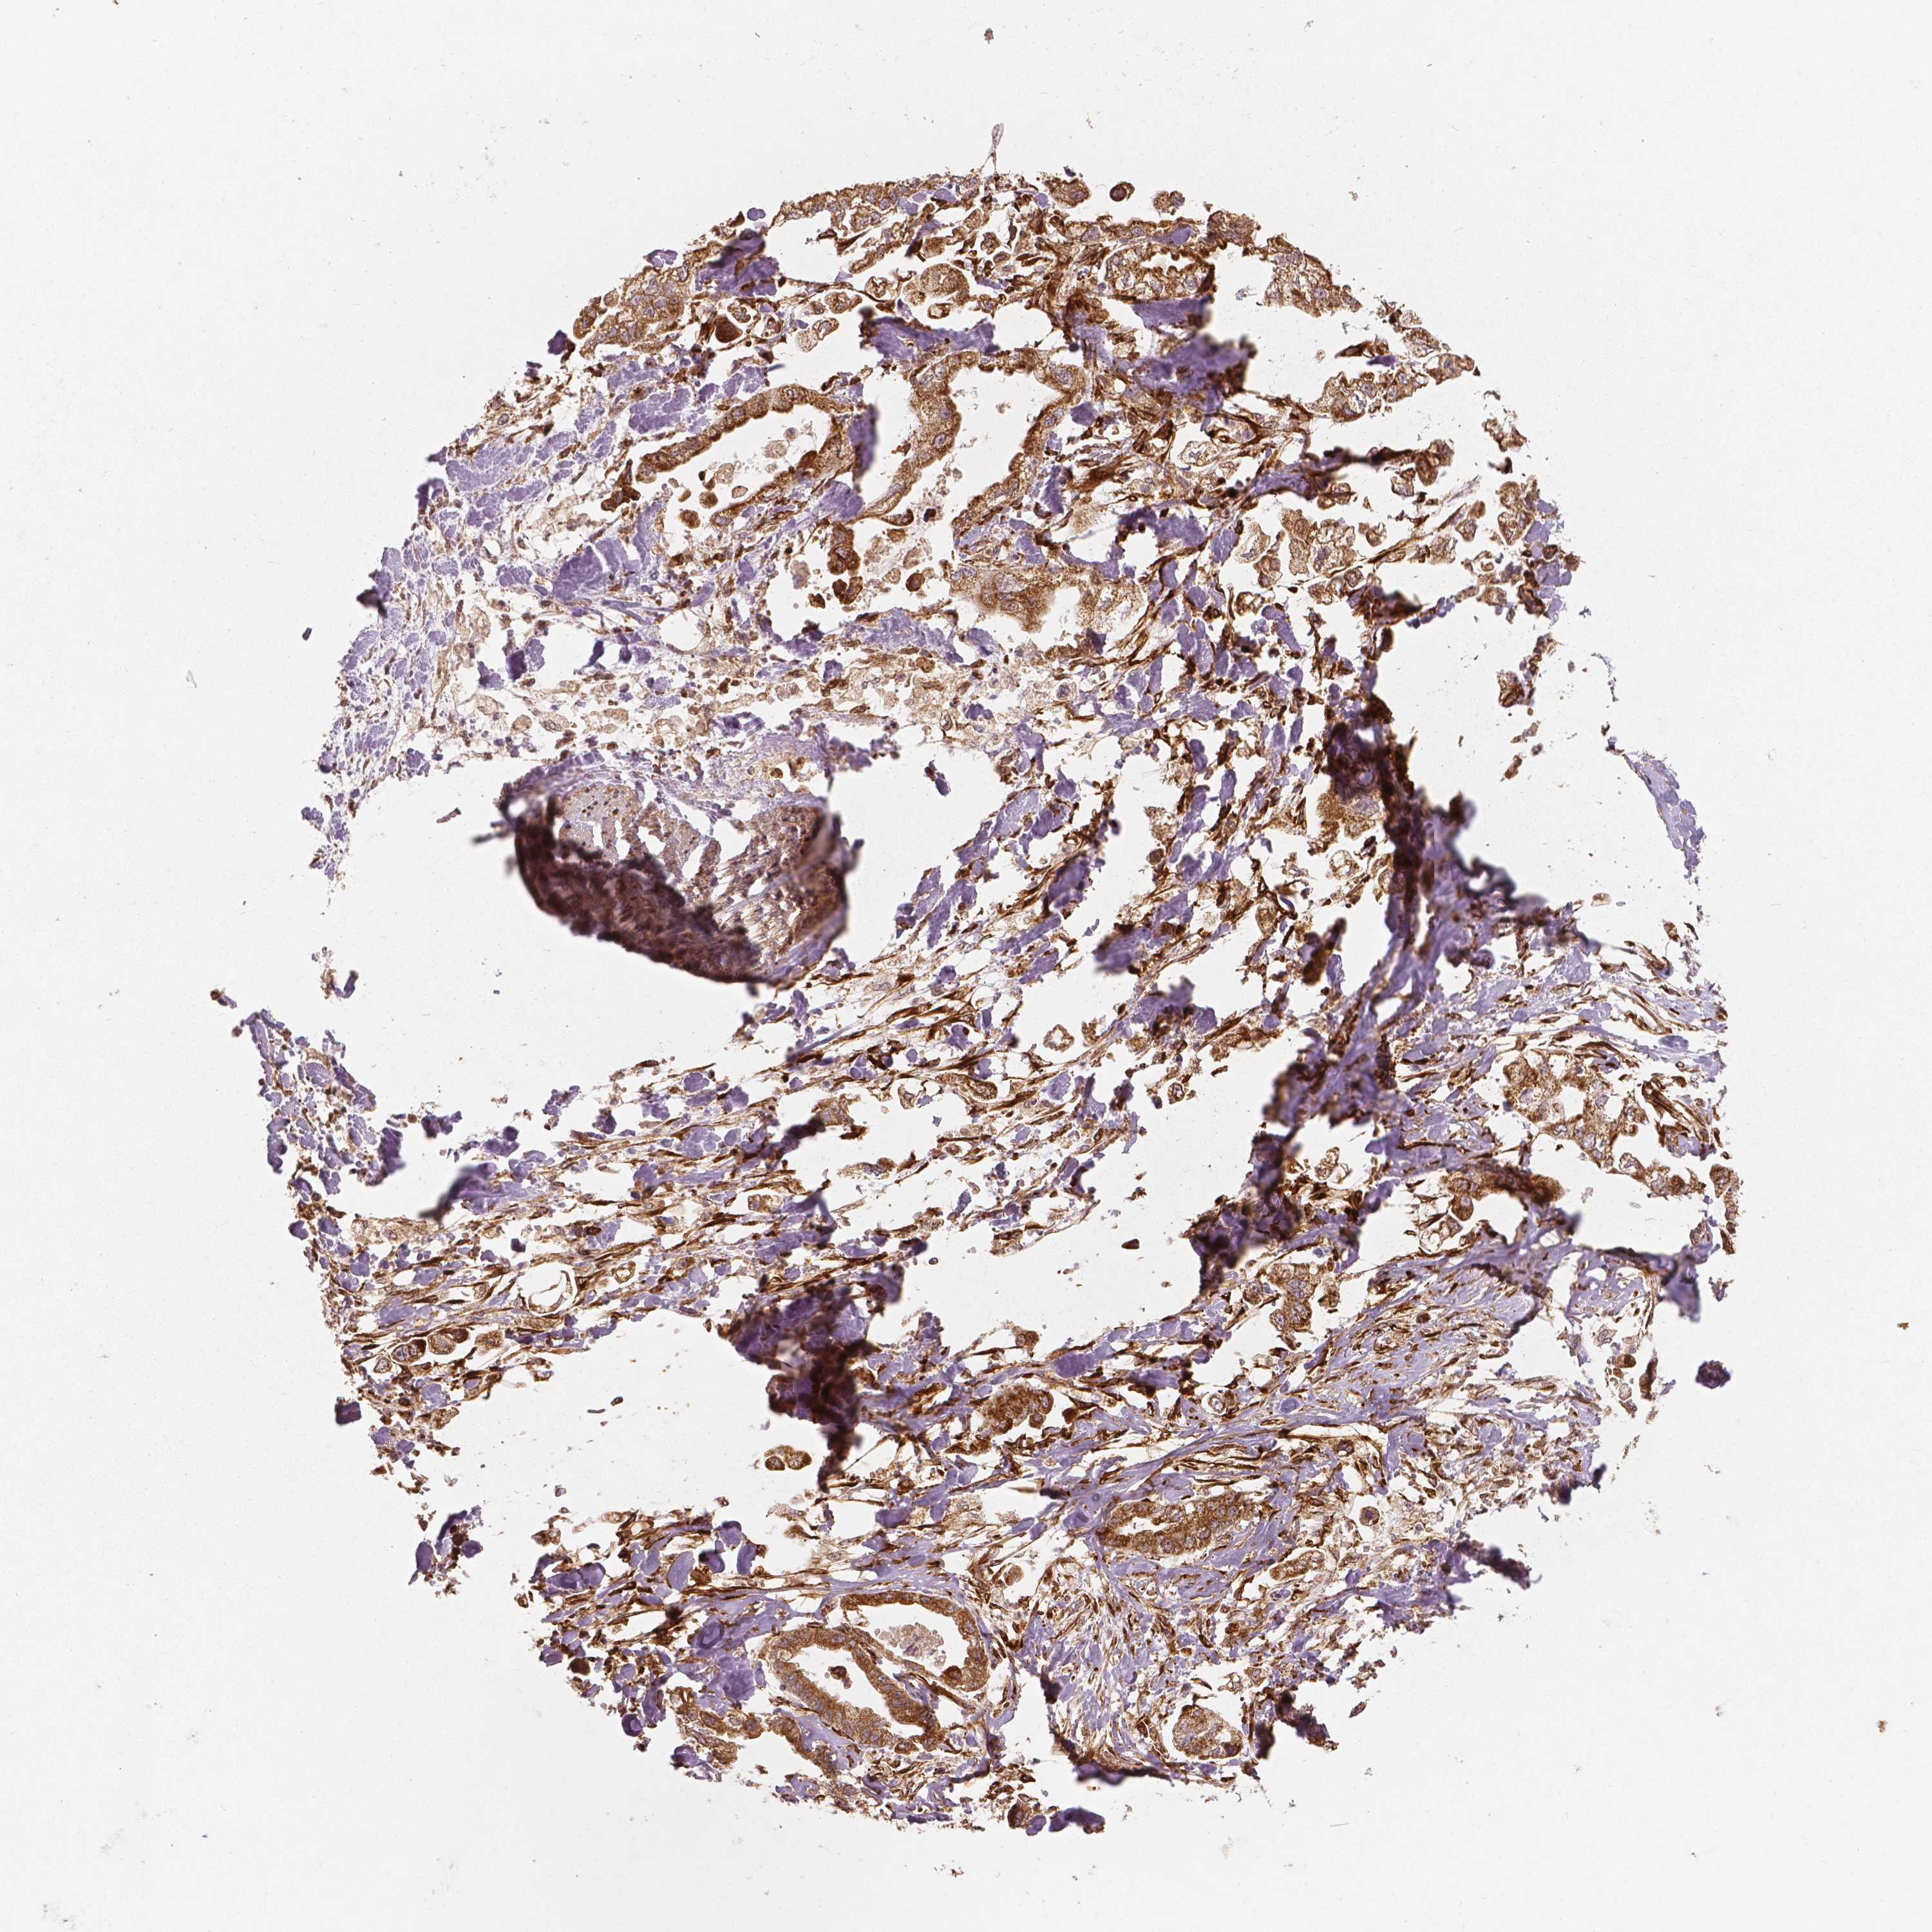

STOMACH CANCER - Protein expressioni

A mouse-over function shows sample information and annotation data. Click on an image to view it in a full screen mode. Samples can be filtered based on level of antibody staining by selecting one or several of the following categories: high, medium, low and not detected. The assay and annotation is described here.

Note that samples used for immunohistochemistry by the Human Protein Atlas do not correspond to samples in the TCGA dataset.

Antibody stainingi

Antibody staining in the annotated cell types in the current human tissue is reported as not detected, low, medium, or high, based on conventional immunohistochemistry profiling in selected tissues. This score is based on the combination of the staining intensity and fraction of stained cells.

Each image is clickable and will lead to virtual microscopy that enables deeper exploration of all samples and also displays staining intensity scores, fraction scores and subcellular localization as well as patient and tissue information for each sample.

Antibody HPA036978

Antibody HPA036979

Antibody CAB068215

Staining

High

Medium

Low

Not detected

Intensity

Strong

Moderate

Weak

Negative

Quantity

>75%

75%-25%

<25%

None

Location

Nuclear

Cytoplasmic/membranous

Cytoplasmic/membranous,nuclear

Adenocarcinoma, NOS